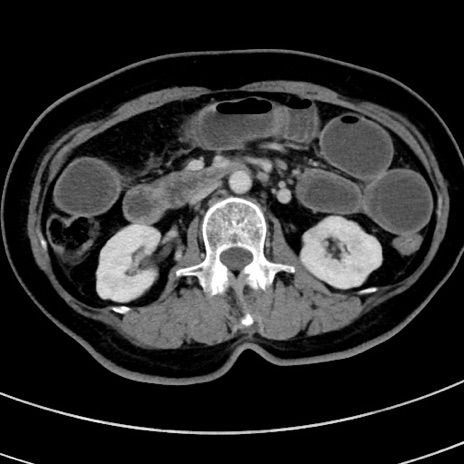

症例9(横断像)

【症例】 60歳代女性

【主訴】むかつき、みぞおちの痛み

【現病歴】3日前よりむかつきがあり、食事がとれない。

【既往歴】糖尿病

【身体所見】発熱なし、心窩部圧痛軽度あるも、腹膜刺激症状なし。

【データ】WBC 7400、CRP 1.92